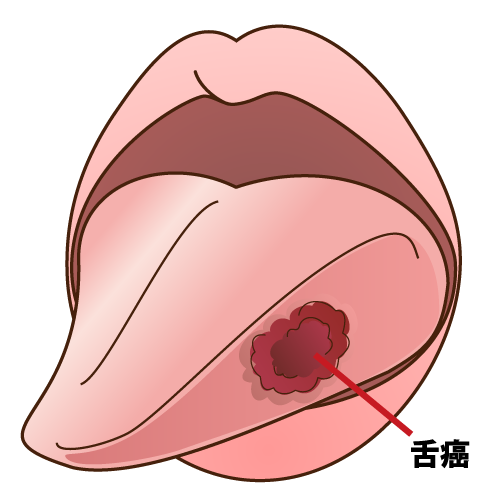

ニコチン性口内炎 舌 (461 無料写真)

ニコチン性口内炎 舌